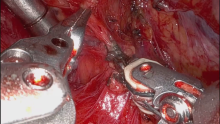

The patient was positioned in the right semi-lateral decubitus position, and a 5 cm incision was made in the sixth intercostal space along the anterior axillary line. After placement of the wound retractor, the robotic arms were inserted, with the camera arm positioned at the top. The robotic arms were defined as follows: the first arm for the left hand, using prograsper forceps; the second arm for the camera; and the third arm for the right hand, using Maryland Bipolar Forceps. The fourth arm was not used.

Dissection began from the inferior part of the mediastinum, and the plane between the mass and the pericardium was dissected with Maryland Bipolar Forceps. Dissection continued between the borders of the bilateral phrenic nerves with safe margins. The thymic veins were detected, encircled, and ligated using Maryland Bipolar Forceps or a bipolar energy device. The thyrothymic ligaments were pulled and divided. The thymectomy was completed, and the specimen was removed from the thoracic cavity using an endobag. Paratracheal lymph nodes were biopsied. A 24 French chest tube was placed through the mediastinum, and the operation was concluded.